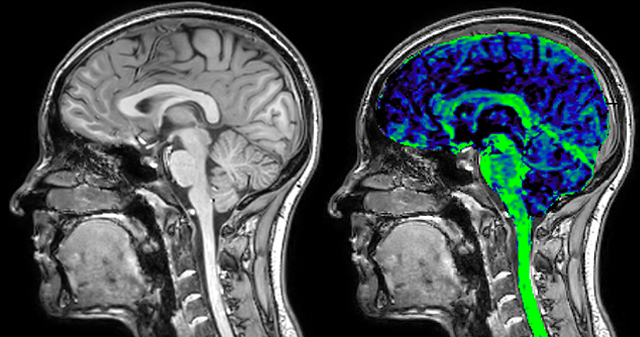

of limiting MWI to the brain, even without the cerebellum, we can now spend about the same amount of time and scan the whole brain and the cervical spinal cord, which is a huge boost for us.” Dr. Rauscher says, “For MWI we perform 3D T2 with 32 or more echoes. This used to take a long time, but with Compressed SENSE we can decrease this to ten minutes for the whole head. Because of the large field of view (FOV) on the readout direction, we even get information from the brainstem, which we previously missed when we were using the GRASE approach. Having the whole head scan is nice because it has spatial resolution, orientation and FOV that are comparable to the standard 3D clinical MS scans, including the FLAIR and 3D T2, and a 3D T1 for brain volume.”

T1 - weighted

Myelin water imaging (echo 1)

With SENSE

With Compressed SENSE

Acquired resolution:

1 x 2 x 5 mm3

→

1.5 x 2 x 3 mm3

Number of echoes:

32 or 48

56

Echo spacing:

10 ms or 8 ms

7 ms

T1 - Weighted, Myelin Water Fraction Superimposed

Spinal cord coverage

Smaller, more isotropic voxels

Excellent detail in quantitative maps

Images courtesy of Adam Dvorak, Department of Physics and Astronomy, University of British Columbia